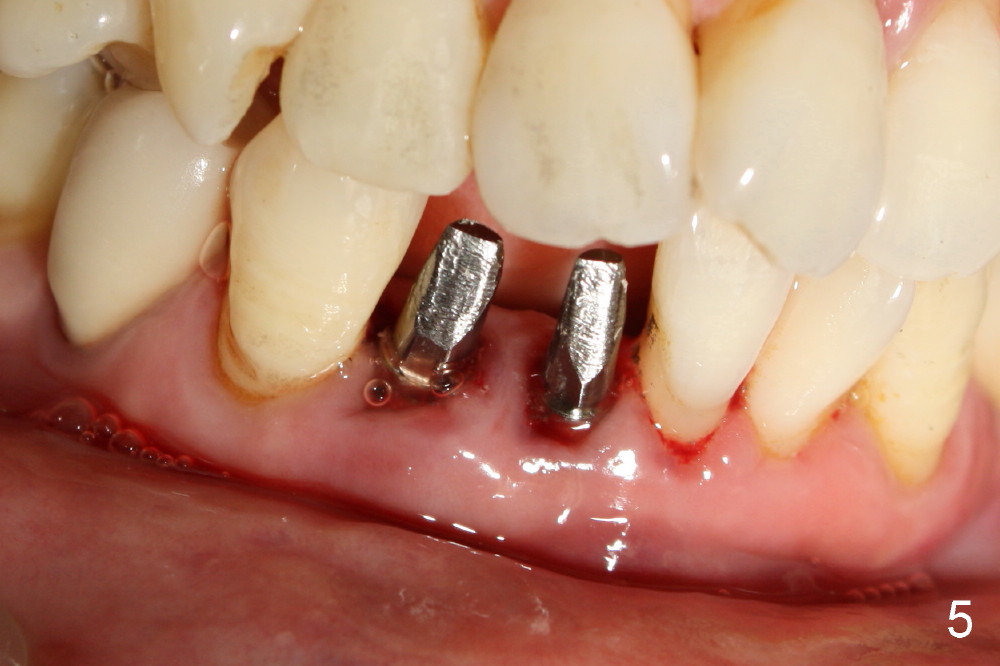

A 60-year-old lady wants to remove 2 mobile lower right incisors (Fig.1,2; with infection at the lateral (>)). Immediate 1-piece implants are placed (Fig.3,4): 3x17 mm at the central, 3.5x17 mm at the lateral. Insertion torque is > 60 Ncm for the implants. No bone graft is placed. After prep (Fig.5), two separate provisionals are fabricated (Fig.6). The one at the lateral incisor looks bulky at the cervix, because of the oversized implant for the site (over-engineering). Use of smaller implant (3.0 (instead of 3.5), 2.5 (instead of 3.0) or 2.0 mm) may solve the problem. Seven days postop, the infection resolves (Fig.7 >) with normal-looking papilla (*).